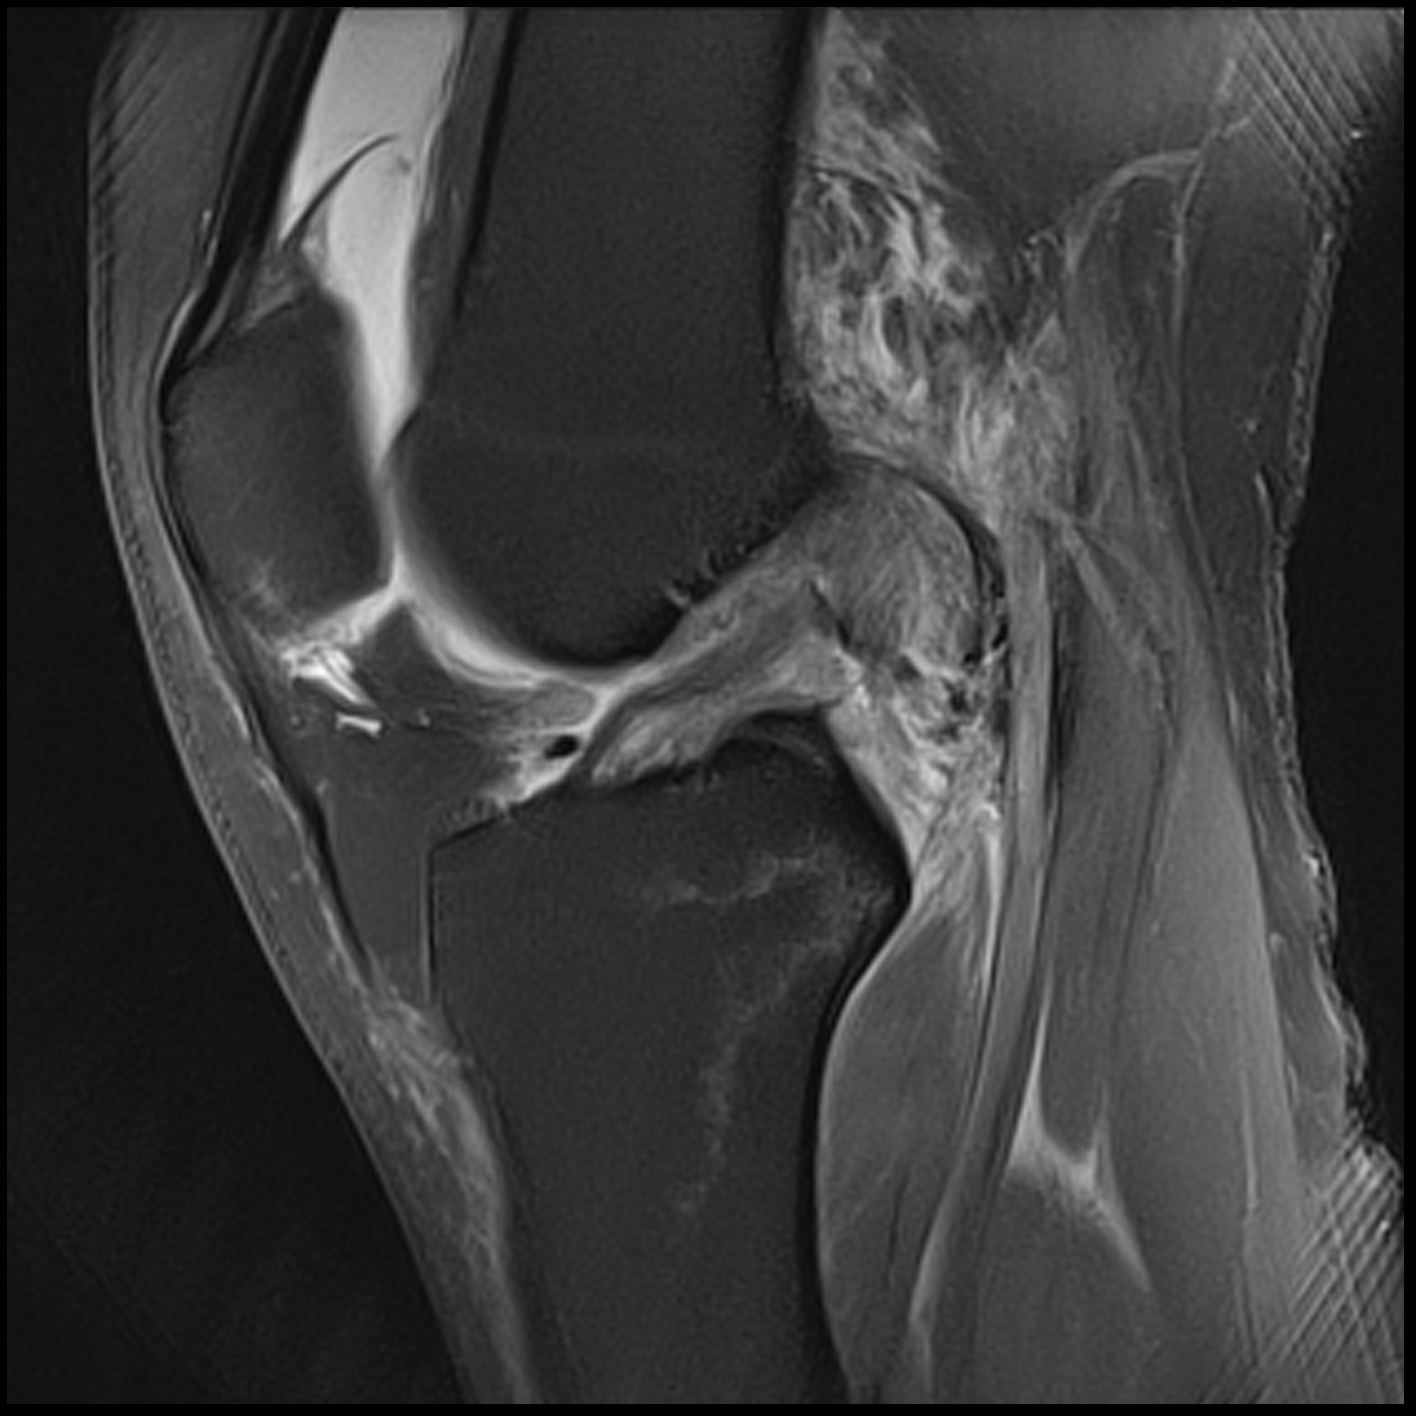

June 2020 MRI

IMPRESSION

- Healed femoral-sided ACL tear with partial attenuation of the proximal ACL fibers.

- Progressive healing of horizontal oblique tear of the medial meniscus posterior horn.

- Chronic inferiorly displaced meniscal flap tear at the lateral meniscus posterior

horn-root junction, less conspicuous than on prior MR imaging. Resolution of previously

noted horizontal longitudinal tear of the body-posterior horn segments. - No new evidence of internal derangement. No acute osseous abnormality.